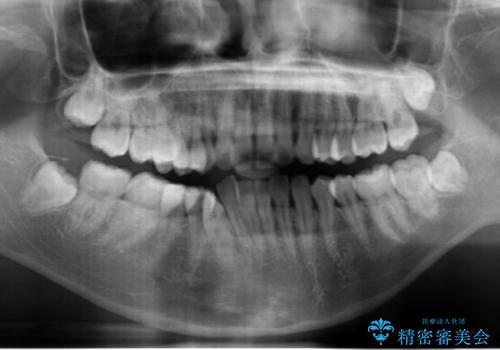

- 歯のがたつきを主訴に来院。

左右とも奥歯のがたつきがあり、左奥はすれ違っていました。

また、右奥は反対咬合になっていました。

インビザライン治療は主に奥歯のかみ合わせが大きな問題がない場合は特に問題なく終了しますが、今回のケースのように奥歯のかみ合わせが悪い場合、しっかり治らないことがあります。

患者様が気づかない範囲で妥協して終わるということをせず、しっかり奥歯に部分矯正を用いて大きな問題を解決してからインビザライン治療に入りました。

下の前歯を一本抜歯しています。(抜歯の本数は最小限にしています。)